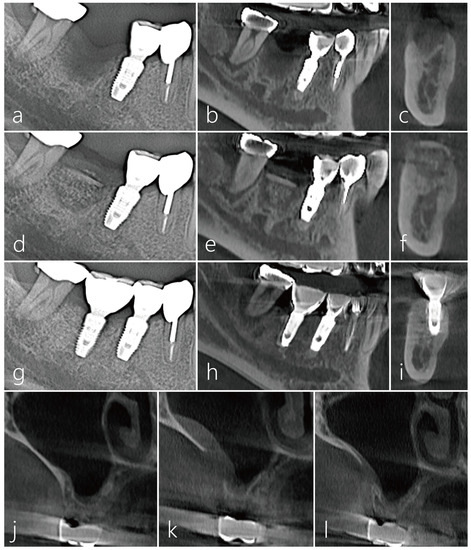

2.3. Case 3

2.4. Case 4